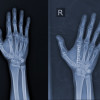

Selamat sore dokter, terkhusus dokter Spesialis Orthopedi

Mohon advisnya dokter

Jadi ada pasien mengeluhkan nyeri seperti tertusuk, tidak selalu, tapi sering, hilang timbul

Pasien post Orif ps H+113/6 bulan (tanggal 06 Agustus 2024)